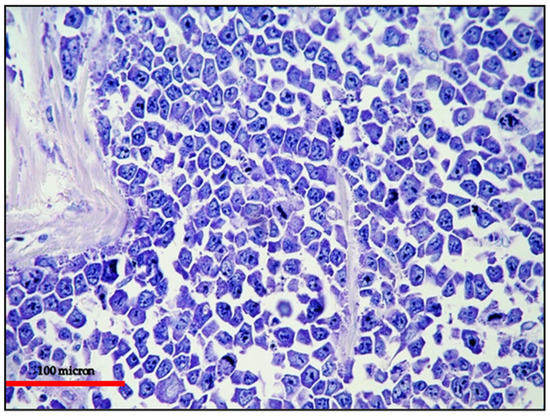

The neoplastic cells generally express plasma cell-related markers, including CD138, MUM18 (Figure 7) and MUM1/IRF4, and markers of lymphoid activation, such as CD30, CD38, EMA and HLA-DR. T-cell markers are usually negative. The aberrant expression of T-cell markers may be observed, and it is more frequent in EC-PEL.

Figure 7.

EC-PEL of the ileum: Diffuse and intense expression of MUM18; similar to PBL, EC-PEL expresses markers of plasma cell differentiation (immunostaining, Ventana immunostainer, magnification 400×; original image from Prof Ascani).